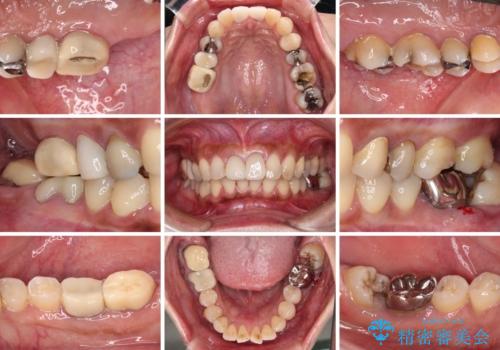

- 奥歯を治療しようと他院で開始したものの、放置してしまったとのことで来院された患者様です。

外れてしまった銀歯や穴の空いた仮歯などあり、適合の悪い被せものと合わせて、セラミッククラウンやセラミックインレーにて治療と行うこととしました。

億劫に感じて治療を先延ばししていたそうですが、始めてみるとスムーズに治療が終わり、早く始めておけば良かったと仰っていました。

他にも加療の必要な歯があるので、定期健診を行いながら再開していく予定です。